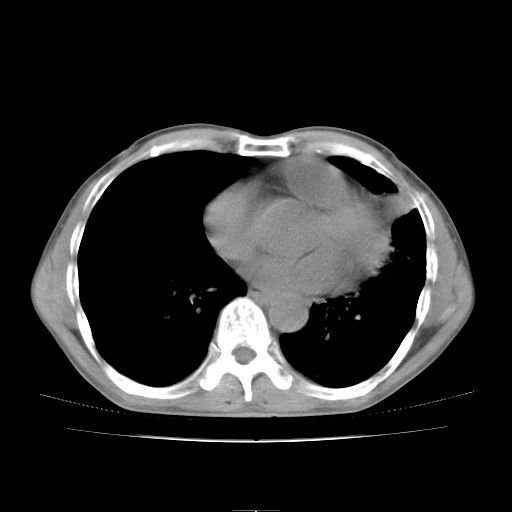

标题: CT25795:感冒后反复咳嗽两月余,痰中带血半月余。X诊断“肺 [打印本页]

标题: CT25795:感冒后反复咳嗽两月余,痰中带血半月余。X诊断“肺

1.双肺肺梗塞(理由:病灶呈三角形,与胸膜相连且局部胸膜肥厚,左心室增大)伴肺感染。

考虑两肺感染性病变,左肺上叶舌段肿瘤性病变待排;建议抗炎治疗后复查。